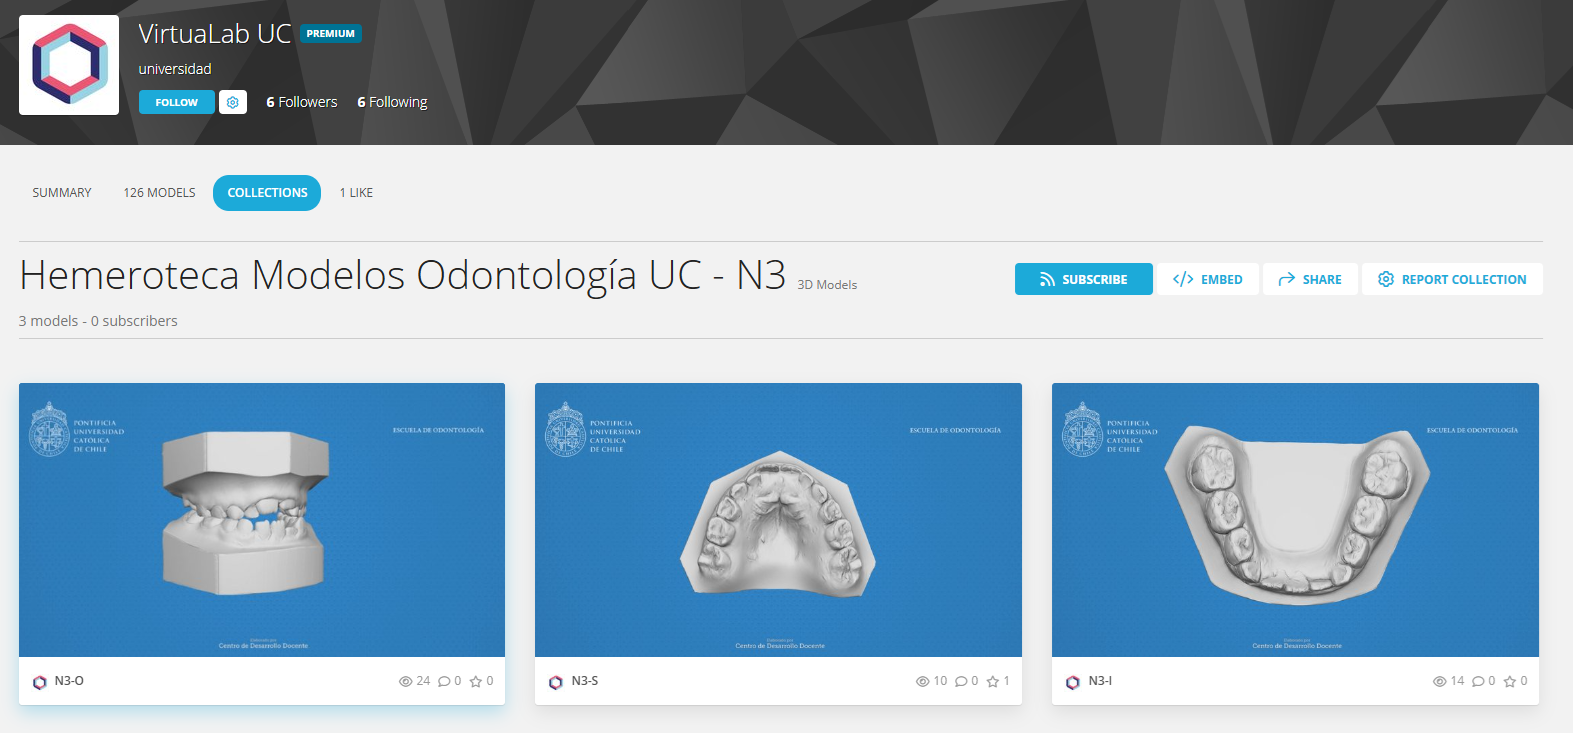

Innovaciones con tecnología

Con el propósito de difundir y masificar el uso de la tecnología en las prácticas docentes UC, en esta sección encontrarás distintas experiencias de aprendizaje, en donde el uso de herramientas tecnológicas ha influido en el éxito del proceso de enseñanza aprendizaje al interior del aula.